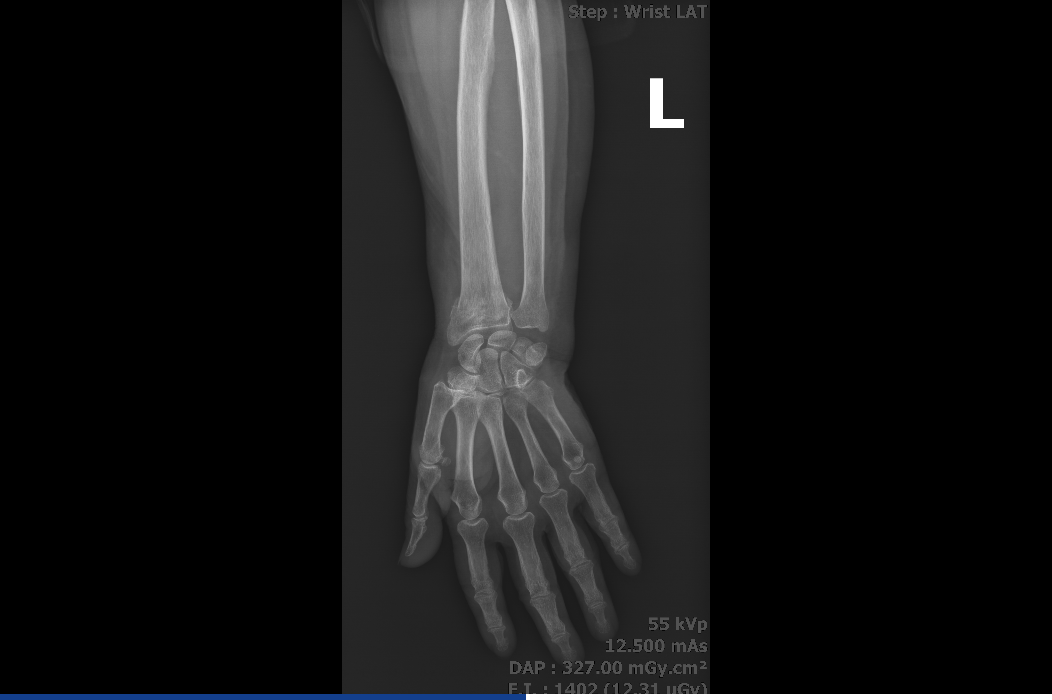

Прикачам и последната направена снимка.

- Прикачени файлове

-

- изтеглен файл (2).png (224.03 KiB) Прегледано 1454 пъти

Потърсете мнение от специалист по образна диагностика или ортопед.